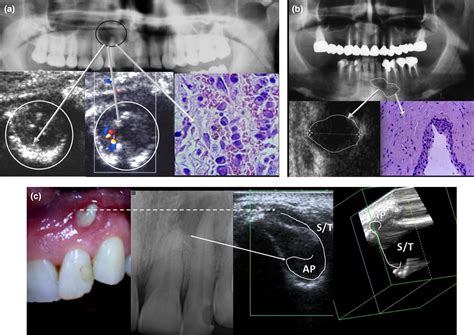

Tooth Periapical Lesion